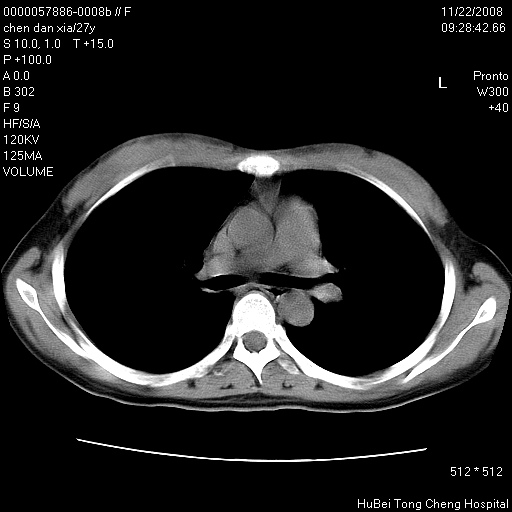

标题: CT16752:F,27Y。发热咳嗽20余天,伴盗汗。 [打印本页]

标题: CT16752:F,27Y。发热咳嗽20余天,伴盗汗。

气管前腔静脉后淋巴结肿大 右肺门纹理模糊

淋巴结核?

右下肺见片絮状影,两肺野内分布不均的小结节影,结核并肺内播散可能性大,建议结合实验室检查 .

右下肺纹理模糊;纵隔可见肿大淋巴节;右心缘旁结节,边缘光滑,纵隔窗病变范围较肺窗明显小,首先考虑右下肺结核,不排外淋巴瘤

下肺结节,结节内钙化,肺门纵隔淋巴肿大 结核可能性大

1)考虑两肺感染性病变。2)纵隔淋巴结肿大。